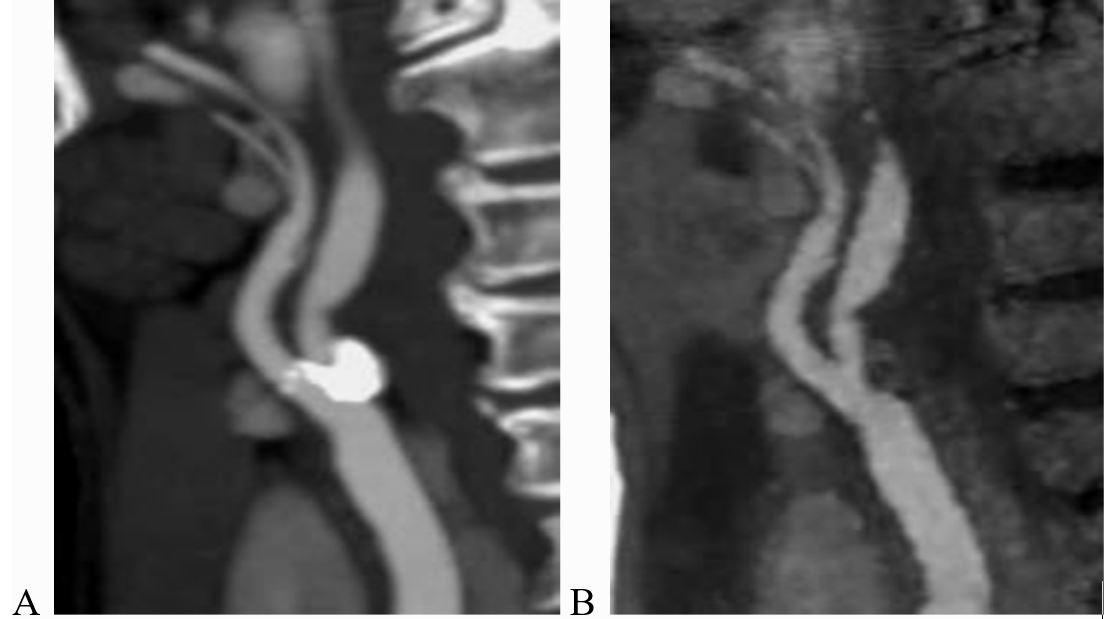

3. Đánh giá mức độ hẹp lòng mạch

Đánh giá lòng mạch trên CLVT thường quy không phải luôn chính xác. Nhiễu ảnh từ các mảng bám vôi hóa và hình ảnh ít thuốc cản quang (i-ốt) ở thì tiêm là các khó khăn thường gặp. Sử dụng hình ảnh CLVT phổ i-ốt xóa can-xi trên máy CLVT Revolution CT 512 dãy cho phép phân biệt tốt hơn giữa calci và i-ốt, cũng như thể hiện được lòng mạch không có can-xi, giúp đánh giá mức độ hẹp lòng mạch (Hình 4).

Hình 4. Hình ảnh chụp CLVT động mạch cảnh

A:Hình ảnh CLVT thường quy ; B: Hình ảnh CLVT phổ i-ốt (xóa can-xi).